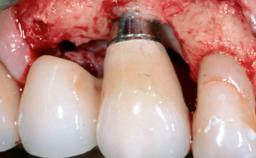

Peri-Implant Mucositis Treatment Outcomes on an Implant with a Submucosal Restoration Margin

Mauricio Araujo and Flauvia Matarazzo present this straightforward clinical case, demonstrating the potential effect of implant placement depth on the resolution of peri-implant treatment. A 42-year-old systemically healthy female patient, a non-smoker with no history of periodontitis, was treated at the Dental Clinic at the State University of Maringá, Brazil between 2008 and 2009, when she received five implants restored with single crowns at sites 14, 26, 27, 36, and 46. After delivery of the implant-supported prosthetic restorations, the patient was enrolled in the supportive peri-implant therapy (SPiT) maintenance program at the same university.